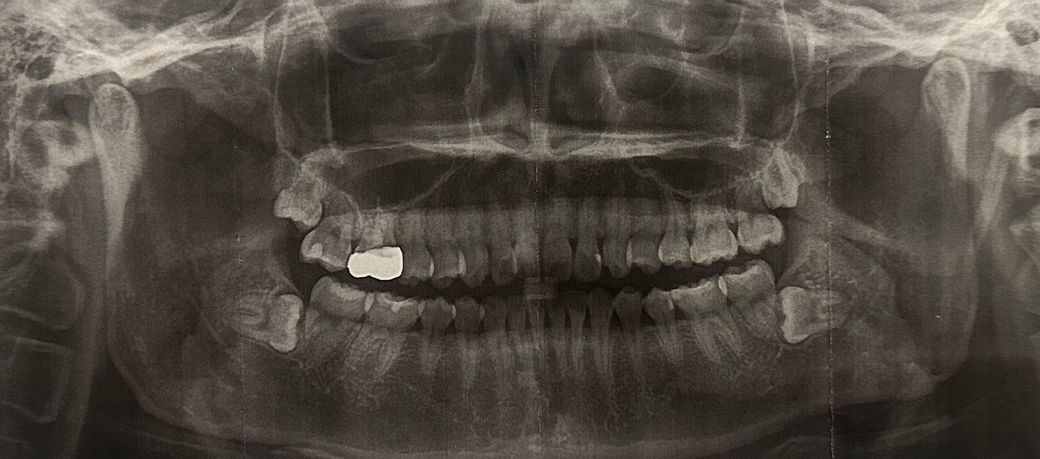

양쪽 수평 매복 사랑니로 인한 앞 어금니 손상 가능성 문의

호주에서 거주 중인데, 아래 양쪽 사랑니가 수평 매복되어 있습니다. 이번에 한국에 들어가면 발치를 고려하고 있습니다.

엑스레이를 첨부합니다.

치과에서는 “사랑니가 앞 어금니 신경을 녹였을 가능성이 있다”라고 하면서, 이런 경우 어금니 임플란트까지 필요할 수 있다고 설명을 들었습니다. 정확히 어떤 상태인지 확인이 필요합니다.

사진으로 봤을 경우에는 사랑니가 치아 뿌리 쪽에 가깝게 위치한 것으로 보입니다. 하지만 아직까지는 앞에 있는 지하의 손상을 입히거나 하지는 않은 것으로 보입니다. 매복된 사랑니의 경우 특별히 문제를 발생시키지 않으면 발제를 하지 않아도 되는 경우가 많습니다.

파노라마 사진 화질이 좋지 않아 아주 명확히 보이진 않으나 사랑니 때문에 그 앞 어금니가 영향을 받았을 확률이 높습니다. 사랑니 발치 후 어금니가 시리거나 하다면 신경치료 가능성 있습니다. 다만 뿌리 흡수가 어느정도 진행된 경우 신경치료 보다 발치 후 임플란트를 할 가능성도 있습니다.

사랑니 발치를 하지 않을 경우 계속 인접 어금니에 영향을 줄 수 있습니다.